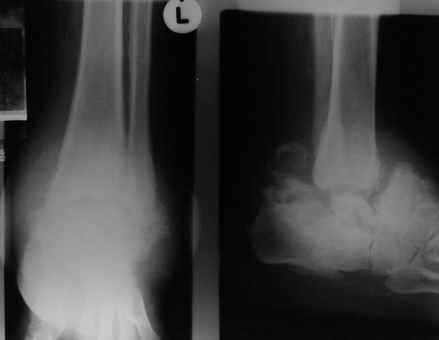

Уажаемые коллеги,представленные рентгенограмммы я показывал на нашем х-рей митинге - они были встречены с большим интересом.. Ну, ещё бы - я сам эту патологии встречал раза три за всю свою долгую жизнь:

VR> Кто шустрый - при какой патологии встречается так называемые <суставы Шарко>?

Сирингомиелия,

Травма спинного мозга

Опухоль

Т.н. нейрогенная артропатия бвает при диабете, периферических нейропатиях, заболеваниях спинного мозга... Как-то довелось вести больного с таким поражением тазобедренных суставов при третичном сифилисе.